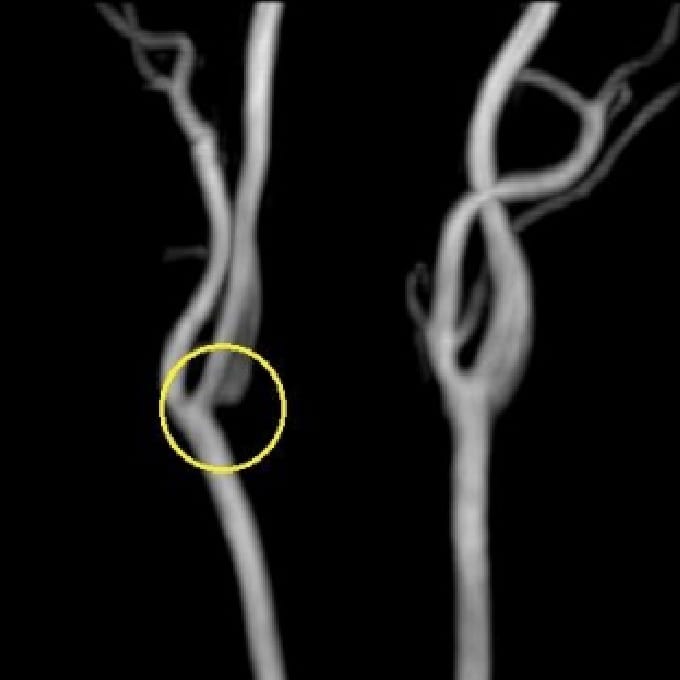

頸動脈狭窄

MRIは、脳の断面画像を撮影し、脳そのものの状態を確認する検査です。X線を使用せず、脳梗塞の痕跡(無症候性を含む)や出血の跡、腫瘍などの異常がないかを調べます。MRAはMRIの撮影法の一つで、脳や頸部の血管を画像として写し出し、血管の形や流れの状態を確認する検査です。未破裂脳動脈瘤の疑い、血管の狭窄・閉塞など、脳卒中リスクにつながる所見の確認に役立ちます。